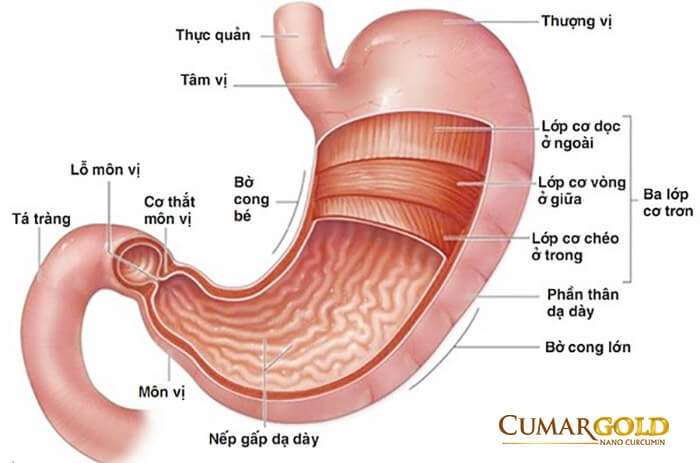

Hang vị là phần nằm ở gần cuối dạ dày còn bờ cong nhỏ dạ dày là phần mép phải của dạ dày, nằm ở vị trí kéo dài từ tâm vị cho đến hết lỗ môn vị. Viêm hang vị bờ cong nhỏ là sự tổn thương vùng niêm mạc ở hang vị ngay vùng mép phải của dạ dày tính từ góc bờ cong nhỏ tới lỗ môn vị. Tình trạng này kéo dài có thể gây ra các bệnh như xuất huyết dạ dày, ung thư dạ dày vô cùng nguy hiểm.

Một trong các lý do bị loét hang vị bờ cong nhỏ hay xảy ra tình trạng loét vì khi bụng đói, dạ dày rỗng, vùng niêm mạc và dưới niêm mạc sẽ tự động co lại tạo thành các nếp gấp khúc. Bờ cong nhỏ của dạ dày là vị trí có nhiều nếp gấp nhất trong dạ dày. Cũng bởi vậy, đây là nơi trú ẩn lý tưởng có các vi khuẩn có hại, giúp chúng dễ dàng ẩn náu và lan rộng dần ra. Vì trú ngụ ở sâu trong cùng của nếp gấp, các vi khuẩn này khó bị tiêu diệt bởi các loại thuốc và cũng không chịu nhiều tác động từ môi trường acid trong dạ dày.

Các tổn thương phát sinh giữa các nếp gấp trong bờ cong nhỏ của dạ dày cũng khó được phát hiện hơn so với các vùng khác trong dạ dày. Do đó, các tổn thương thường không được điều trị khi mới phát sinh mà chỉ khi viêm loét nặng, chúng ta mới phát hiện được và điều trị.